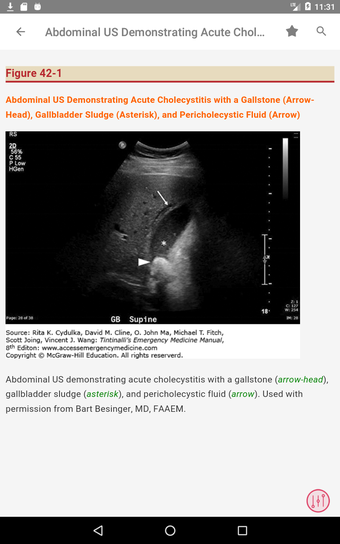

この無料アプリには、日常の実践に役立つ多くの情報が含まれています。このアプリでカバーされるトピックは、疾患から薬剤、さまざまなタイプの傷害まで幅広く、患者ケアを担当する人々にとって素晴らしいリソースです。